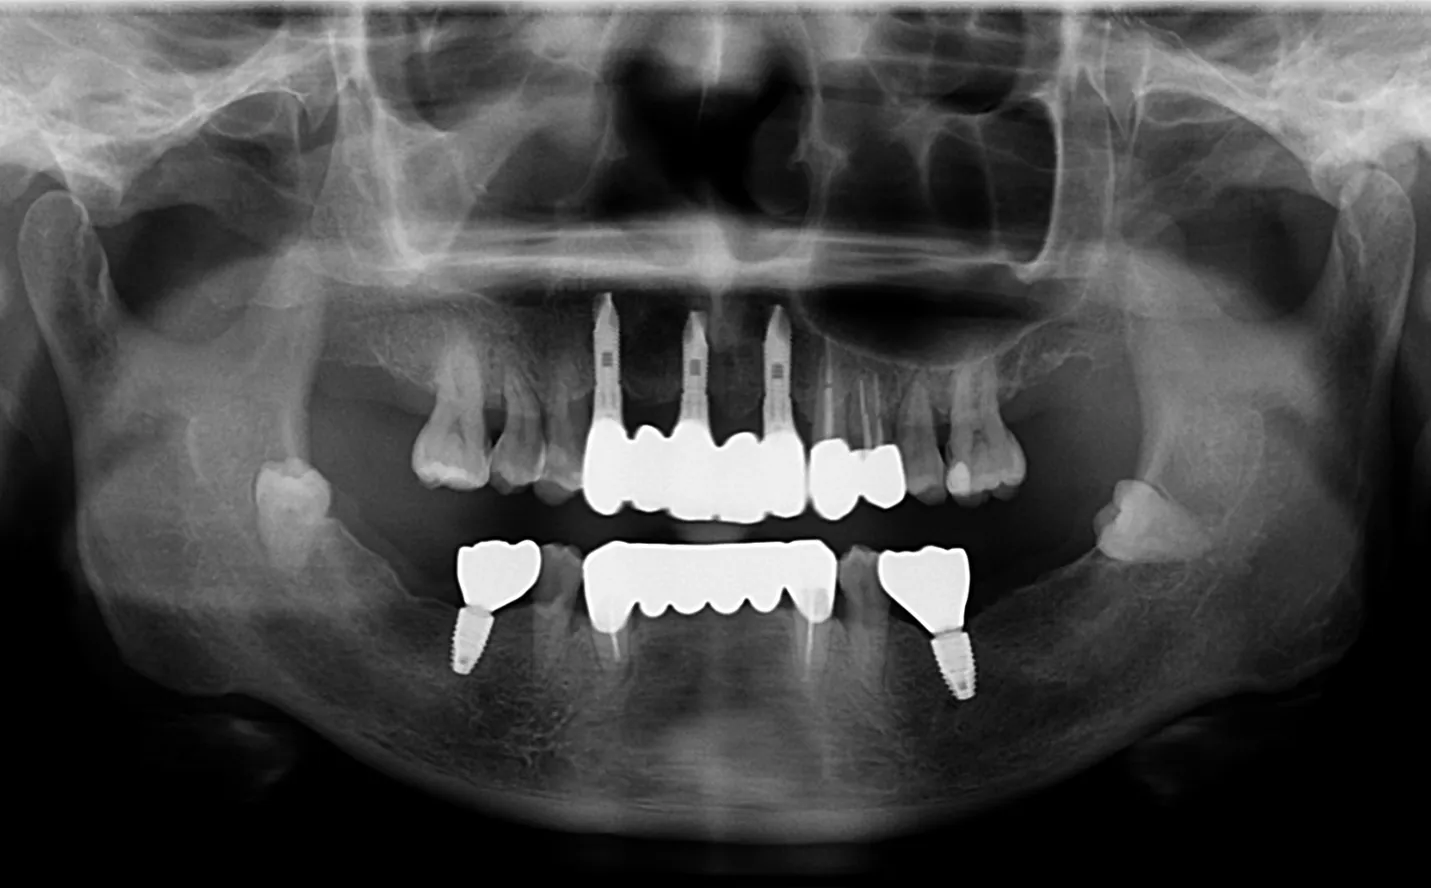

【症例2】

主訴

前歯の被せ物が外れた。綺麗に治したい。

年齢・性別

40代男性

治療内容

右上3~左上2に対して

・インプラントブリッジ

左右6に対して

・インプラント

他数本に対して

・セラミック

期間

1年4ヶ月

費用

3,583,000円